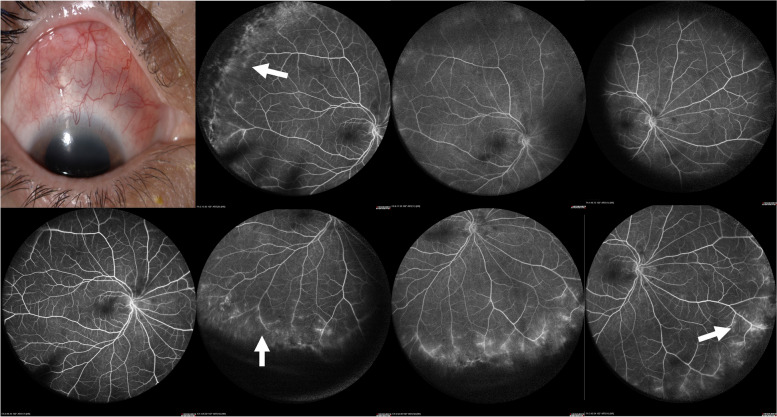

目的:描述在活动性前巩膜炎患者中出现宽视场荧光素血管造影(WFFA)的比例。方法:对活动性前巩膜炎患者的WFFA检查结果进行观察性、描述性、横断面研究,包括结节性、弥漫性或坏死性受累。研究使用海德堡光谱仪模块(102º)进行。图像由两位蒙面的共同作者保存和评估。结果:39例患者79只眼,女性31例(79%),平均年龄50.5岁±13.98岁。平均最佳矫正视力(BCVA)为0.1343±0.2475 logMar或20/27。39.58%的活动性巩膜炎眼和16.66%的非活动性巩膜炎眼存在WFFA。全身相关性为50%,与anca相关的血管炎最为普遍。WFFA结果在前弥漫性巩膜炎病例中更为常见,并与中枢性和外周性巩膜渗漏的巩膜严重程度相关(p结论:近40%的前巩膜炎患者有血管渗漏的WFFA结果,无巩膜炎的患者有16%。视网膜血管渗漏需要作为前巩膜炎患者局部和/或全身性活动的标志进行探索,并可能对疾病的严重程度和管理产生影响。

Objective: Describe the proportion of patients with wide-field fluorescein angiographic (WFFA) findings in patients with active anterior scleritis.

Methods: An observational, descriptive, cross-sectional study of the WFFA findings of patients with active anterior scleritis including nodular, diffuse, or necrotizing involvement was performed. Studies were performed with the Heidelberg Spectralis module (102º). Images were saved and assessed by two masked co-authors.

Results: Seventy-nine eyes from 39 patients, 31 (79%) females with a mean age of 50.5 years ± 13.98. Mean best-corrected visual acuity (BCVA) of 0.1343 ± 0.2475 logMar or 20/27. WFFA findings were observed in 39.58% of eyes with active scleritis and in 16.66% of eyes without scleritis. Systemic association was present at 50%, with ANCA-associated vasculitis being the most prevalent. WFFA findings were more frequent in cases of anterior diffuse scleritis and correlated with scleritis severity when central and peripheral leakage (p < 0.022) and cystoid macular edema (p < 0.013) were present.

Conclusions: Almost 40% of eyes with anterior scleritis have WFFA findings of vascular leakage and 16% of eyes without scleritis. Retinal vascular leakage needs to be explored as a sign of local and/or systemic activity in patients with anterior scleritis and may have implications for disease severity and management.